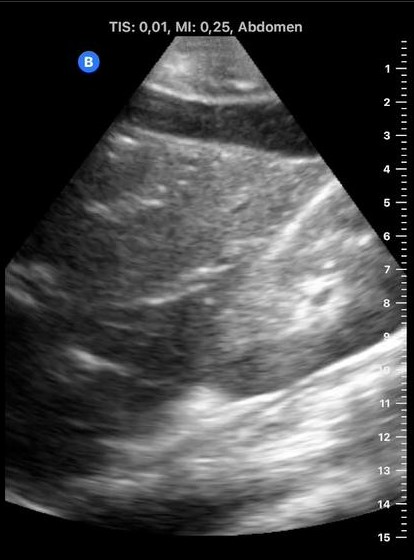

Vemos contenido anecogénico poco limpio bajo cúpulas diafragmáticas sobre todo en ambos flancos. Hígado con vasos portales muy birrefringentes. Riñón izquierdo algo desestructurado pero con difícil ventana.

La paciente ingresa en observación para tratamiento analgésico y preparación para cirugía urgente. En la analítica no presentaba leucocitosis pero sí reactantes de fase aguda elevados. Previa a la cirugía se realiza TAC abdominal con objeto de localizar la posible perforación que aparecía en antro gástrico y en la cirugía se objetiva el líquido ascítico purulento compatible con las imágenes captadas en ecografía.